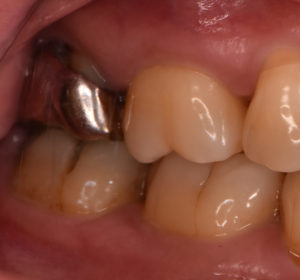

全顎的に診査したところ右上の一番奥の歯に虫歯と根尖病変をみとめました。たまに違和感を感じるとのことで治療を行っていきました。また不適合な補綴物の境目のところに歯石の付着もみとめます。虫歯でほとんど歯質が残っていない状態と考えられますが、再治療を行い歯の保存を行うこととしました。

治療方法:不良補綴物を除去した後、う蝕を除去・隔壁形成した後ラバーダム防湿下にて根管治療を行った。根管内の感染物質を除去した後、通法に従い根管充填した。根尖病変の経過観察を行った後、ジルコニアセラミッククラウンにて歯冠修復を行った。その他全顎的な虫歯治療や歯周治療も行った。

すでに根管治療がされているの歯の再治療例になります。再根管治療の目的は、根管内の感染物質を取り除くことにあります。精度の良いジルコニアセラミッククラウンでの再修復により、根管内に再度感染源が侵入するのを防ぎ、根尖病変の再発を防ぐことで長く歯を使用することが可能となります。